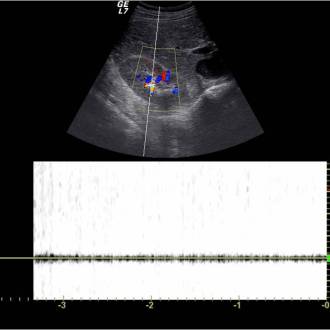

La ECOGRAFÍA es una técnica que se utiliza en muchas especialidades para el diagnóstico de las diferentes patologías características de las mismas. Su uso ha sido ampliamente extendido por su eficiencia: gran rendimiento diagnóstico con bajo coste y ausencia de complicaciones.

En lo concerniente a la especialidad de Aparato Digestivo y gracias a los modernos aparatos, la ECOGRAFÍA ofrece una gran rentabilidad diagnóstica tanto en su vertiente positiva, diagnóstico de enfermedades, como en la negativa, ausencia o despistaje de éstas.

Disponemos de un equipo de ecografía que tiene Sistema Doppler en sus diferentes versiones, una sonda “Convex” y otra “Lineal de Alta Frecuencia”. Cualquiera que sea la solicitud o indicación de la exploración ecográfica, independientemente de una especial atención sobre la misma, se investigará sobre la normalidad o patología de las siguientes estructuras anatómicas: Vesícula…